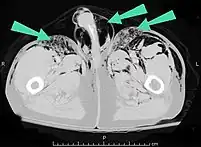

An abdominal CT scan of a patient with subcutaneous emphysema (arrows)

Subcutaneous air (arrows) can be seen as black areas on this pelvic CT scan.